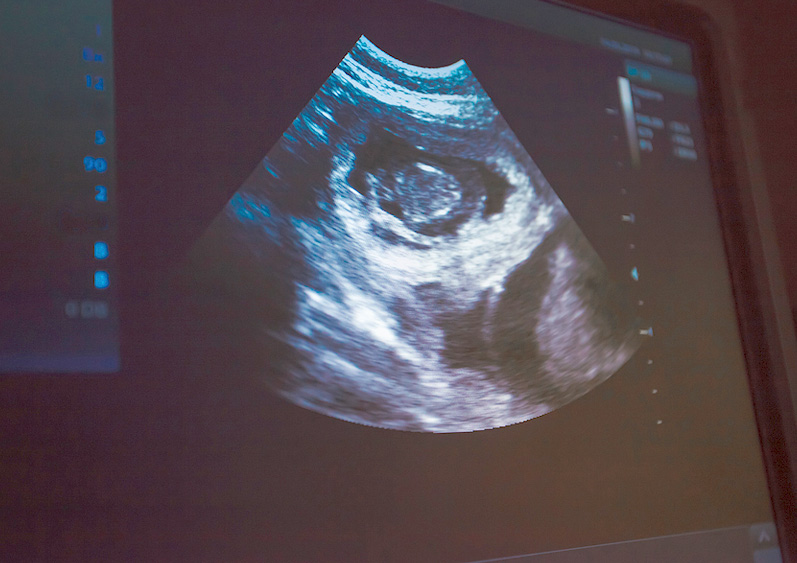

L’échographie, en revanche, permet de visualiser les organes internes en temps réel grâce aux ultrasons. Elle est particulièrement utile pour observer des tissus mous comme le cœur, le foie, ou les reins. Contrairement à la radiographie, l’échographie offre une vue dynamique, permettant au vétérinaire de suivre les mouvements des organes, par exemple les battements du cœur ou le flux sanguin.

À l’échographie :

- Corps étranger

- Masse anormale abdominale

- Maladie rénale

- Effusion abdominale